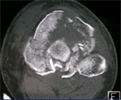

Pre

Op

CT Scan